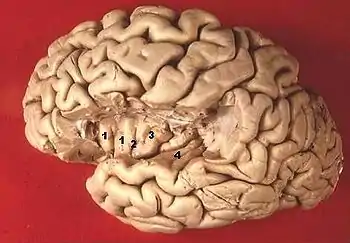

| (fig.3) Vue de la face supérieure de T1 et de l'insula après résection d'une partie du lobe frontal et pariétal 1,2,3 : gyrus de l'insula 4 gyrus temporal transverse |